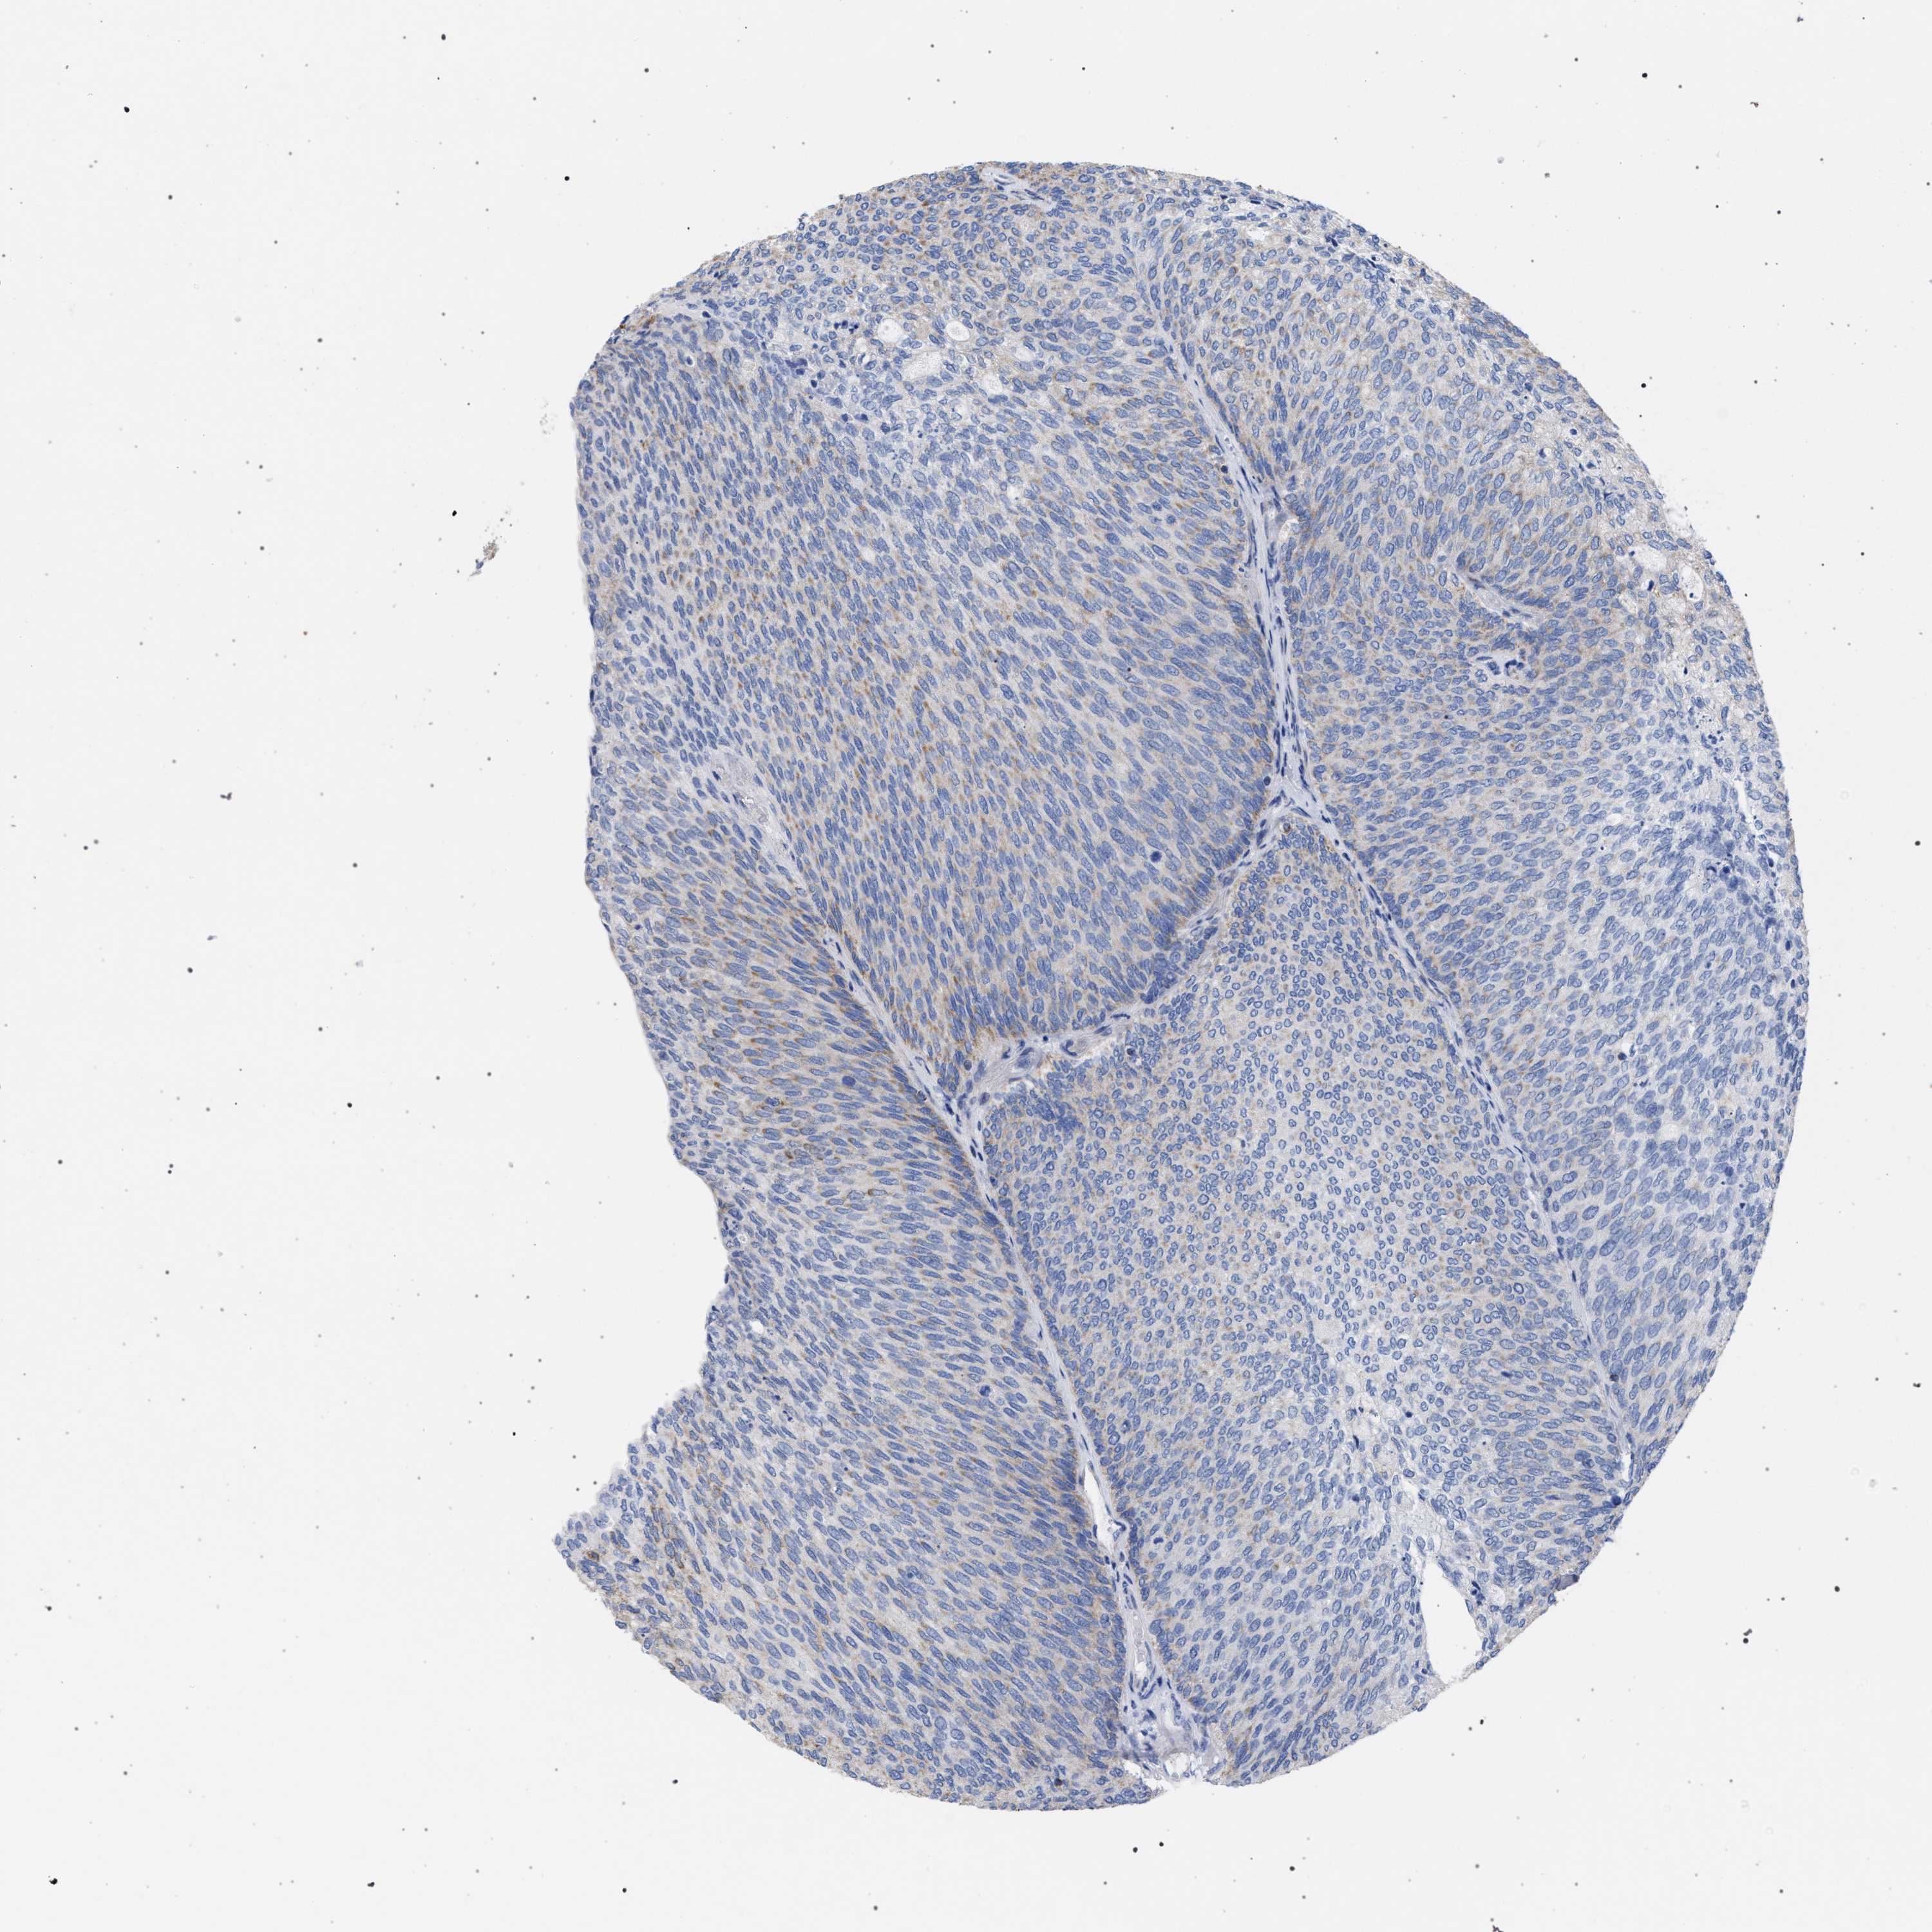

UROTHELIAL CANCER - Protein expressioni

A mouse-over function shows sample information and annotation data. Click on an image to view it in a full screen mode. Samples can be filtered based on level of antibody staining by selecting one or several of the following categories: high, medium, low and not detected. The assay and annotation is described here.

Antibody stainingi

Antibody staining in the annotated cell types in the current human tissue is reported as not detected, low, medium, or high, based on conventional immunohistochemistry profiling in selected tissues. This score is based on the combination of the staining intensity and fraction of stained cells.

Each image is clickable and will lead to virtual microscopy that enables deeper exploration of all samples and also displays staining intensity scores, fraction scores and subcellular localization as well as patient and tissue information for each sample.

Antibody HPA022271

Antibody CAB019284

Urothelial carcinoma, Low grade

Urothelial carcinoma, High grade